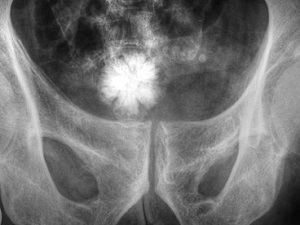

El objetivo de este estudio publicado en el número 1 del volumen 11 correspondiente a 2022, de la Revista Cubana de Urología, es identificar la presencia de algunos factores de riesgo reconocidos para padecer litiasis urinaria en una población cubana.

Se realizó un estudio prospectivo, descriptivo y transversal, de enero de 2020 a julio de 2021, como parte de un proyecto de investigación que pretende crear una escala de riesgo para padecer litiasis urinaria en una población cubana. Se estudiaron 140 pacientes del sur de Ciego de Ávila, que consultaron por litiasis urinaria.

En los resultados se observó que predominaron los pacientes ≥ 40 años (68,5 %), las mujeres (50,8 %), los de piel blanca (85,8 %), sobrepeso u obesos (69,2 %) con historia familiar de litiasis (80,7 %). El 33,6 % tenía daño de la función renal y el 16,4 %, cifras de glucemia elevada. Se constataron altos niveles de fósforo en sangre en 70,7 %; de ácido úrico, en 34,3% y de calcio, en 27,1%; en tanto que las cifras de magnesio estaban disminuidas en 43,6 %.

Sin embargo, tenían niveles elevados de calcio y fósforo en orina el 30,7 % y 31,4 % respectivamente; el magnesio y volumen urinario estaban disminuidos en 57,1 % y 35,7 % respectivamente.

Los autores concluyen que los factores de riesgo para padecer litiasis urinaria identificados en la población estudiada fueron la edad, el color de la piel, sobrepeso, historia personal de litiasis, fósforo sérico elevado y magnesio en orina disminuido.